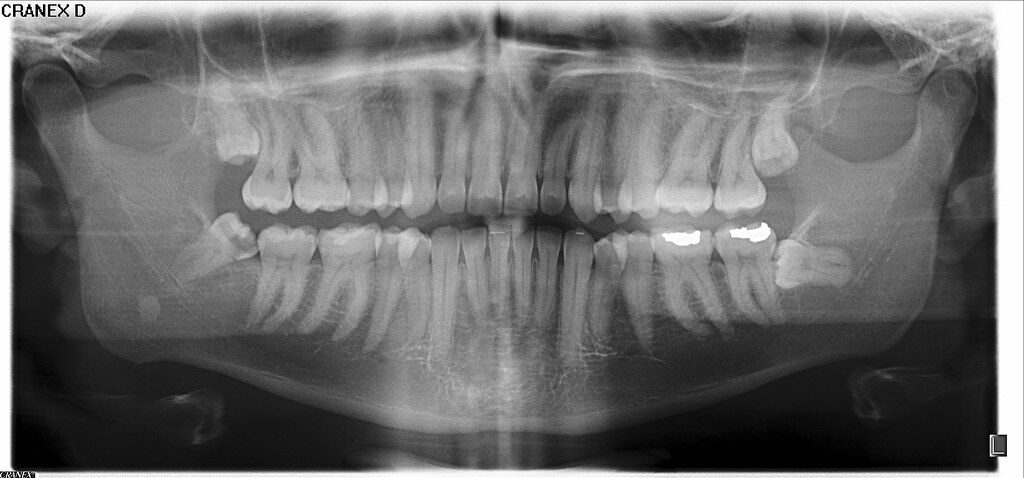

Our Digital X-Ray Department is equipped with modern imaging technology that provides clear, high-resolution images within minutes. Digital X-rays use significantly less radiation than traditional methods, ensuring patient safety while maintaining diagnostic accuracy. This advanced system allows our doctors to identify fractures, chest infections, joint problems, and other internal conditions with enhanced clarity and speed.

All X-ray images are digitally processed and securely stored, making it easy for physicians to review and share results when needed. Our trained radiology technicians ensure proper positioning, comfort, and safety throughout the procedure.

Digital sensors are used instead of traditional photographic film. This technology allows for faster image processing, improved image clarity, and easier storage and sharing of images.